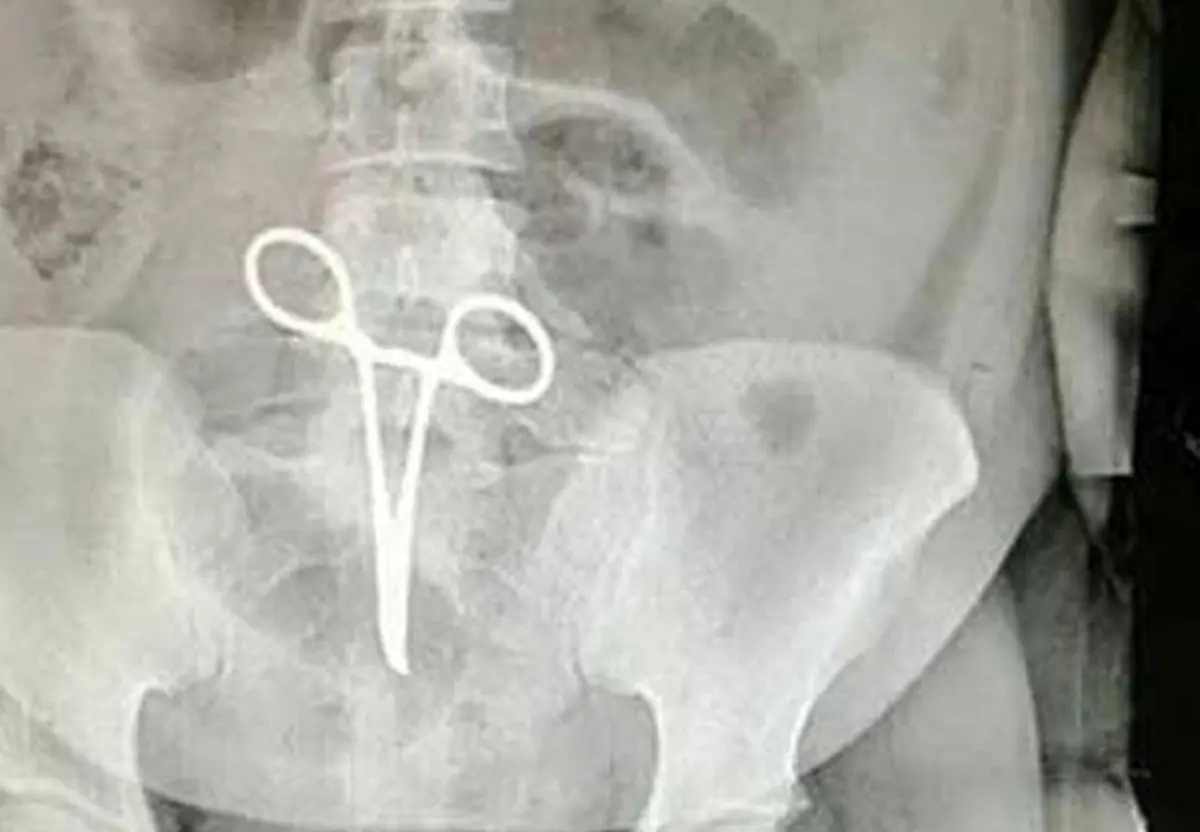

وی بابیان اینکه اشتباه رخ داده یکی از موارد نادر پزشکی بود که تاکنون در این بیمارستان اتفاق نیفتاده بود، افزود: بعد از اینکه عکس از ناحیه شکم بیمار گرفته میشود همکاران متوجه جسم خارجی(پنس) در داخل شکم بیمار میشوند.

رئیس بیمارستان شهید بهشتی اردستان، ادامه داد: بدون هیچ فوت وقتی مقدمات عمل جراحی سوم انجام میشود و عمل جراحی و عملیات بیرون آوردن پنس توسط پزشک جراح که این بیمار را عمل کرد انجام میشود.